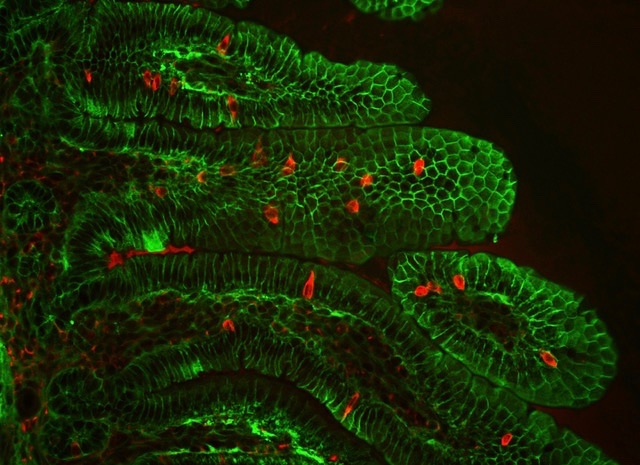

National Center for X-ray Tomography at the ALS

Our soft X-ray tomography capabilities generate detailed 3D maps of the structures inside cells, down to individual organelles.